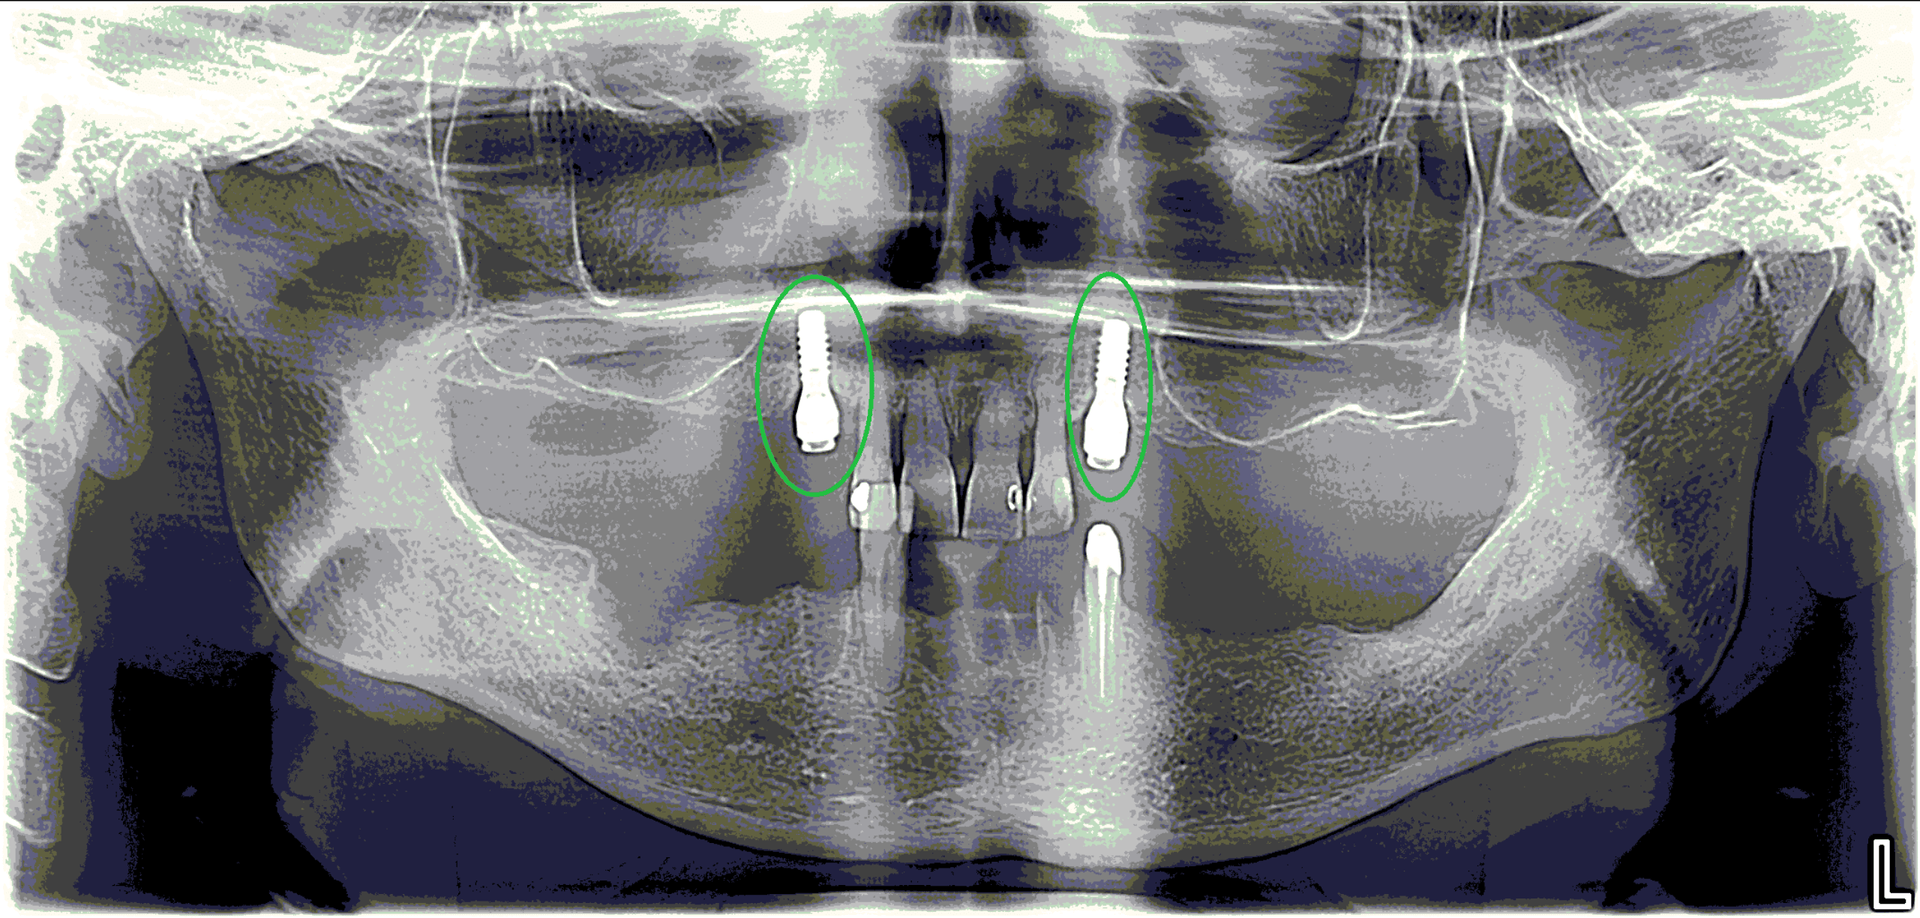

Unsere erfahrenen Zahnärztinnen setzen moderne digitale Röntgengeräte ein. So können aussagekräftige Röntgenbilder erstellt werden. Zudem profitieren Sie von einer deutlich geringeren Strahlenbelastung.